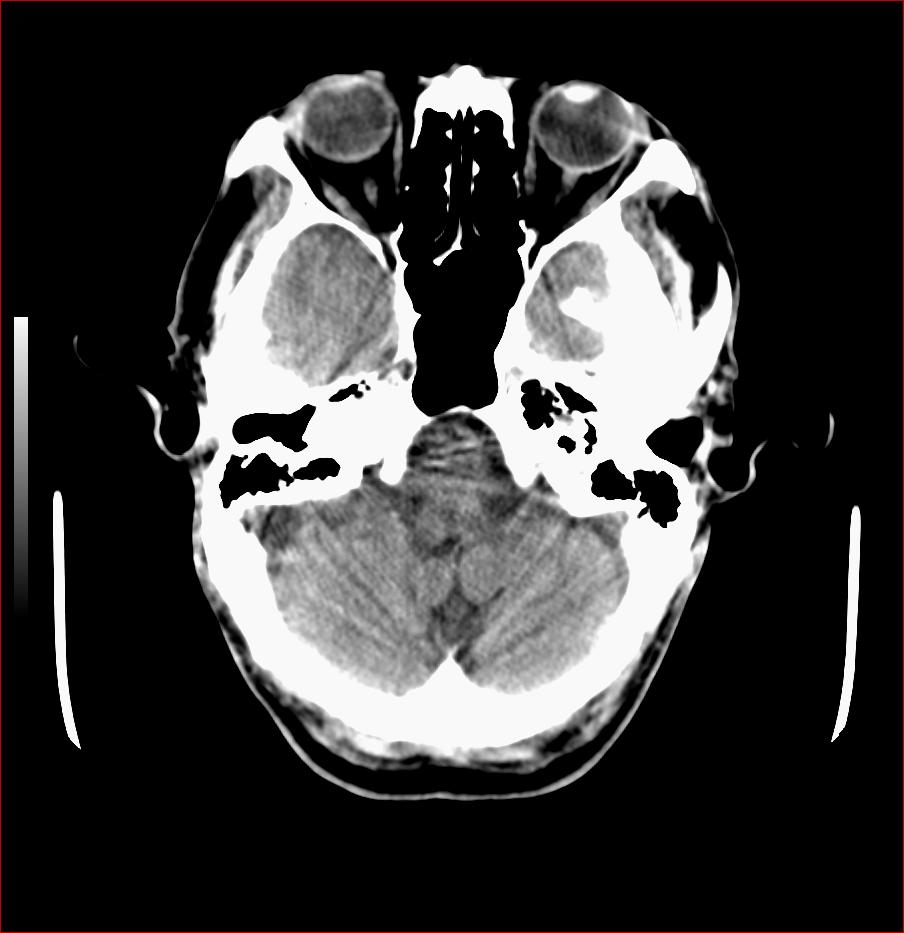

男,84岁,左下肢无力伴口角歪斜1天,血压160/80。请问一下双侧基底节区是脑梗塞吗?

基底节区脑梗塞,脑萎缩,左侧小脑脑梗塞

右侧基底节区斑片状低密度影,边缘模糊,结合临床考虑:1.右侧基底节区脑梗塞;2.老年性脑改变。

1.两侧基底节区及右顶深部脑梗塞。2.右侧外囊区脑软化灶。3.脑萎缩。4.脑白质脱髓鞘改变。

右侧基底节区斑片状低密度影,边缘模糊,结合临床考虑:1.右侧基底节区脑梗塞;2.老年性脑改变